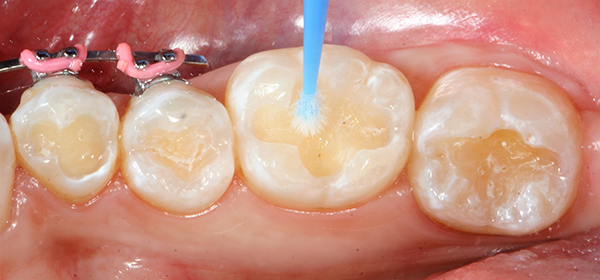

After the two separate one-minute applications of disinfectant, the restorations were suctioned to achieve a damp surface.2 This step was followed by the application of OptiBond™ All-In-One self-etching dental adhesive by KaVo Kerr with Ball-Point Applicators (Fig 2 ).

I used OptiBond All-In-One self-etching adhesive because it combines the ingredients needed for etching, priming and bonding into a single adhesive solution, thereby eliminating separate etching and priming steps of the bonding process.3 It’s extremely easy to use and its bond strength is consistent. I’ve had no reports of post-operative sensitivity using this bonding method.

Using the Ball-Point Applicators, I applied a generous amount of OptiBond All-In-One adhesive to the enamel/dentin surface. I scrubbed the surface with a brushing motion for 20 seconds, and then applied a second application of OptiBond All-In-One adhesive with a brushing motion for 20 seconds. I then dried the adhesive with gentle air first and then medium air for five seconds with oil-free air, and then light cured for 10 seconds with the Kerr Demi™ Plus Curing Light (Fig. 3).

Fig. 3 Fig. 4